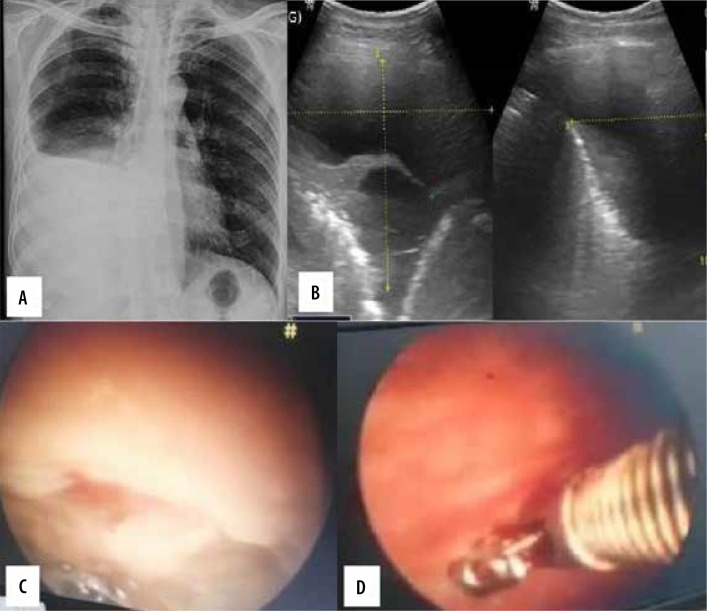

Purpose: The purpose of this study was to evaluate the use of the transthoracic ultrasonography (US) for pleural adhesions and pleural thickening and to quantify pleural effusion by standardised sonographic techniques and its comparison with thoracoscopic findings. An assessment of the association between pleural thickness and pleural nodularity with histopathological examination findings was also attempted.

Material and methods: Thirty-one patients with suspected chest pathologies were initially assessed by transthoracic US followed by videothoracospy. Findings observed were noted and appropriately analysed statistically.

Results: Transthoracic US is 100% sensitive and specific for detecting pleural septations in the presence of pleural effusion with 100% accuracy. Gliding sign is a highly sensitive and specific sign to detect the pleural septations in absence of pleural effusion. There was no significant association of thickness of pleural septation with the pleural malignancy.

Conclusions: Transthoracic US plays an important role in the quantification of pleural effusion, assessment of the pleura and pleural space for pleural adhesion, pleural thickening, and guiding trocar insertion.